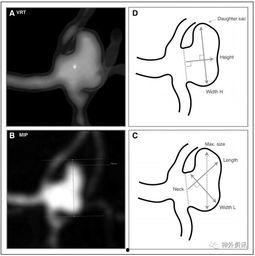

3. 动脉瘤:动脉瘤是动脉壁局部膨胀形成的囊状结构,如果破裂,后果不堪设想。